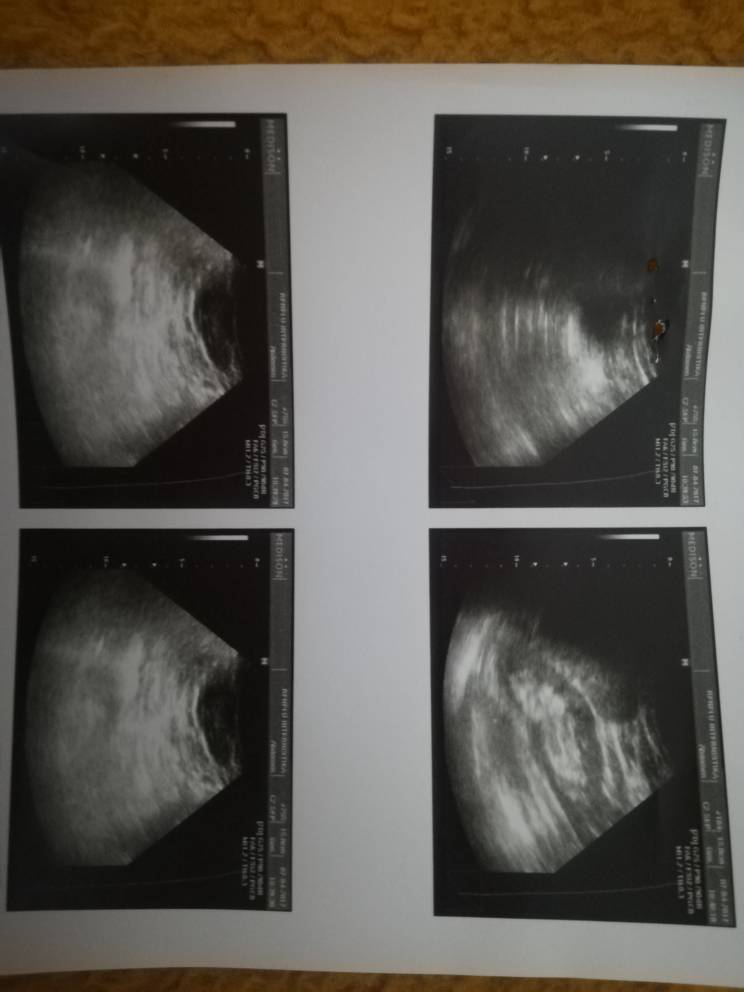

Прво фала ти што ми одговори. Незнам дали се гледа на документите кои ги прикачив погоре, дијагнозата беше каскаден желудник и хеликобалтер опилори со 4 плуса. За кила на желудник не ми кажаа ама ми го рекоа истото што ми го кажа сега, повеќе помали оброци на ден и не јадење доцна на вечер пред легнување. Е сеа ја ги осеќам тегобите најмногу во движење, седење/стоење, нагло станување, наведнување, многу поретко или ич во лежечка положба. Печење осеќам високо во градите под врат и лево и десно во висина на рамо или само од лева страна во предел на брадавица. Анализа на крв праев ама незнам дали е правена проверка на шеќерот (ќе прикачам анализа подолу), а сега кога го спомна да осеќам како нагло опаѓање на притисок, лутина/како ментол ладно во нос и како да дишиш на празно(незнам како да го доловам чувството)

Незнам дали ртг снимки се овие ама се ехо снимки од абдомен. Ако не се каде би можел да направам и да ми кажат дали е тоа проблемот. Фала ти уште еднаш